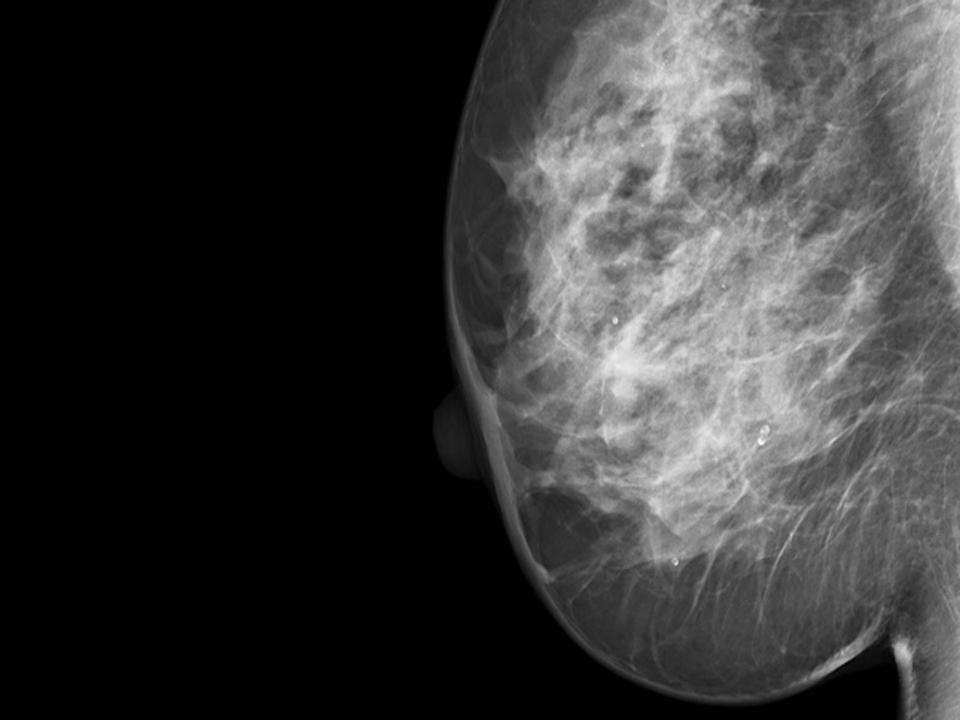

Clear analysis of dense breast tissue